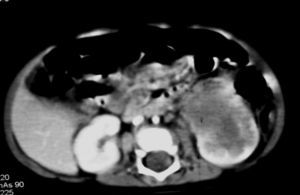

El sarcoma de células claras tuvo lugar en un niño de 2 años estudiado por masa abdominal, en el que se identificó una masa intrarrenal, de predominio necrótico y una adenopatía retrocava (fig. 8).

Fig. 8. Sarcoma de células claras. Tomografía computarizada abdominal con contraste intravenoso. Corte sobre polo inferior renal. Masa en riñón derecho, sólida, hipodensa, con gran crecimiento extrarrenal y que desplaza colon ascendente hacia delante (flechas). Adenopatía retrocava, hipodensa (A) de 3 cm.